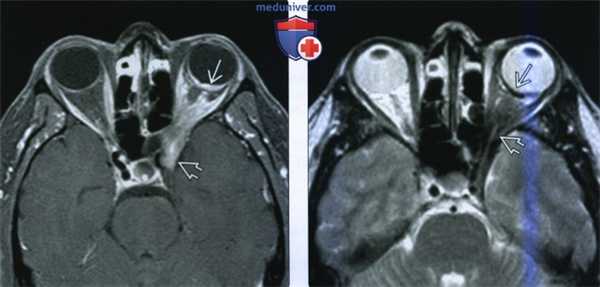

(Слева) При МРТ Т1 ВИ в аксиальной проекции, полученной с помощью отдельной катушки для глазницы, в носовом квадранте заднего отрезка правого глазного яблока определяется гиперинтенсивное объемное образование с четкими контурами. Грибовидная форма опухоли и наличие «перетяжки» у ее основания с высокой вероятностью указывают на инвазию опухоли сквозь мембрану Bruch.

(Справа) На микропрепарате под малым увеличением видна грибовидная меланома, прорастающая сквозь мембрану Бруха. Также видна массивная экстраокулярная опухоль, распространяющаяся кзади через головку зрительного нерва.